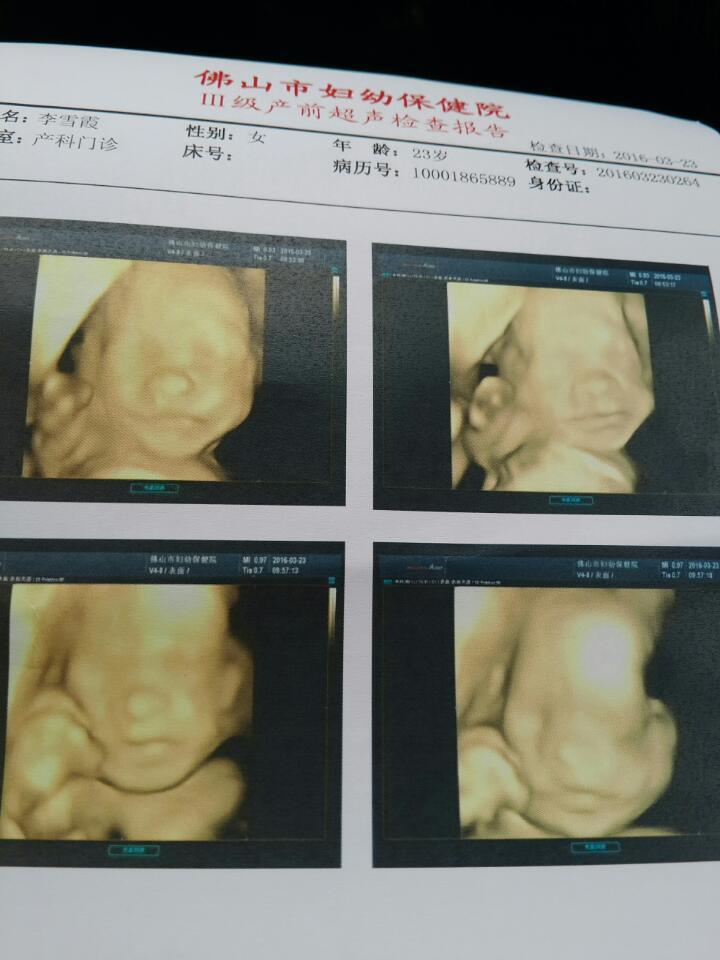

预产期下个月18号 大家来猜猜这是男的还是女的?其实男女我都喜欢,只是好奇而已 预产期下个月18号。大家来猜猜这是男的还是女的?其实男女我都喜欢,只是好奇而已。 点击展开 夏强520 2016-06-30 13:27 为您推荐: 其他回答 恭喜 恭喜 玉醉凝馨 2016-07-30 19:38 祝宝宝健康! llbaby2 2016-07-29 21:39 恭喜恭喜! llbaby2 2016-07-29 21:39 恭喜恭喜! CZ相博.雨 2016-07-29 17:44 恭喜。。。。 59...6@qq.com_6sJW 2016-07-29 16:51 加载更多 相关问题 这是前几天的B超单,有会看男女的宝妈吗?预产期都过了11天了,宝宝还没动静,很好奇是男还是女,会看 我和老公都是属龙的,给龙年宝宝起名还不知男女,预产期今年4月18日的预产期!请高手帮忙 郎姓预产期6月18号男女龙宝宝